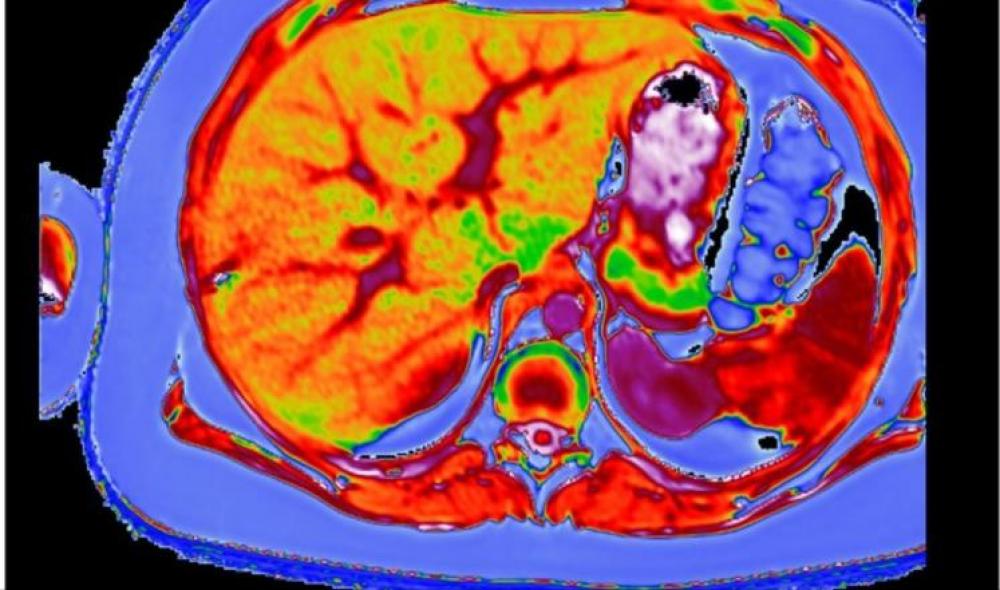

أظهرت دراسة حديثة أن بريطانيا تشهد ارتفاعا وبائيا في مرض الكبد الدهني غير الناجم عن الخمر (non alcoholic fatty liver disease)، في وقت يتناول فيه الناس كمية من الطعام أكبر مما تستطيع أجسامهم التعامل معها، ونشرت الدراسة من قبل الاتحاد الأوروبي.

ويقدر أن مرض الكبد الدهني غير الناجم عن الخمر يؤثر في نحو ثلث سكان بريطانيا، وأن الكثيرين من المصابين لا يعرفون أنهم مصابون بالمرض.

ويعد المرض أحد المسببات الخمسة الأولى للموت في بريطانيا، بالإضافة إلى السرطان ومرض القلب والسكتة الدماغية.

ولا يؤثر المرض في الأشخاص البدناء فقط، بل يشمل أيضا الأشخاص الذين يعانون من زيادة بسيطة في الوزن.

ويقول المختص في أمراض الكبد كوانتين أنستي إن المرض يرتبط بالطعام والإفراط في الأكل، مضيفا أنه يؤثر في 94% من الأشخاص البدناء، وفي 25% من الذين يعانون من زيادة بسيطة في الوزن.